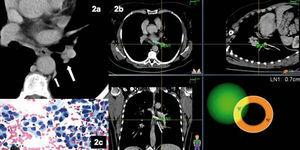

Mujer de 52 años de edad, no fumadora, que acudió a consulta para valoración de un nódulo pulmonar. Se le había diagnosticado recientemente de artritis reumatoide seronegativa y presentaba enfermedad de Von Willebrand. Se realizó una TC torácica sin contraste, motivada por un cuadro de tos y disnea persistente. En el escáner se objetivó una pequeña lesión de 1 cm de tamaño, paraaórtica, sin adenopatías visibles (fig. 2). En nuestro centro se realizó una tomografía por emisión de positrones, que evidenció captación no sólo del nódulo pulmonar ya conocido, sino también de la región hiliar izquierda. Por este motivo se planteó la realización de una broncoscopia diagnóstica con navegación electromagnética, previa administración profiláctica de desmopresina. Se efectuaron 3 punciones con aguja citológica y el anatomopatólogo estuvo presente durante la exploración (fig. 2). Se diagnosticó un adenocarcinoma de probable origen pulmonar.

Fig. 2. Imagen de tomografía computarizada convencional(a), que iden-tifica la presencia de un nódulo pulmonar paraaórtico inaccesible (flecha pequeña) y un ligero engrosamiento hiliar izquierdo (flecha gruesa) que resultó hipercaptante por tomografía por emisión de positrones. Imagen de navegación(b)con la sonda (flecha) a 0,7 cm de la adenopatía, que permite realizar una punción transbronquial. El anatomopatólogo, presente durante la exploración, confirmó que se trataba de un adenocarcinoma (c).